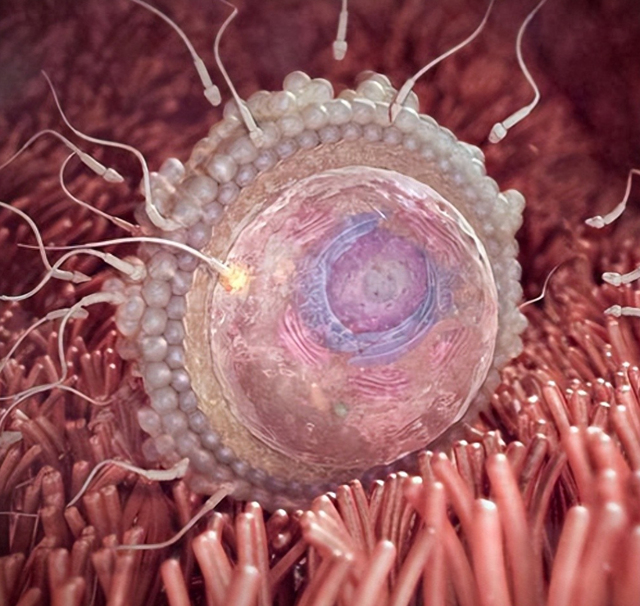

孕1周:受精

精子是令嫒万马过独木桥,最终见到卵子的精子豪爽只须几十到几百颗,而这几十几百颗勇往直前地扑向卵子,然则最终只须一颗精子能成为卵子的入幕之宾。